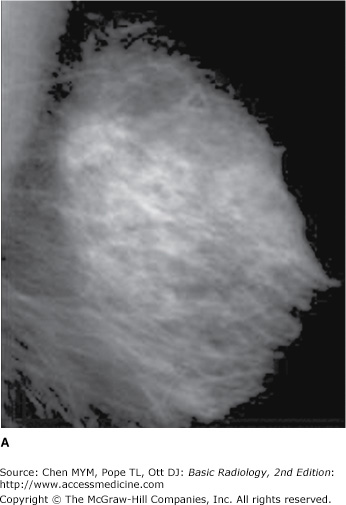

A) Mammogram showing dense breast tissue. (B) MRI of same breast showing enhancing cancer in otherwise minimally enhancing breast.